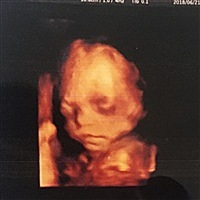

孕33周+4天